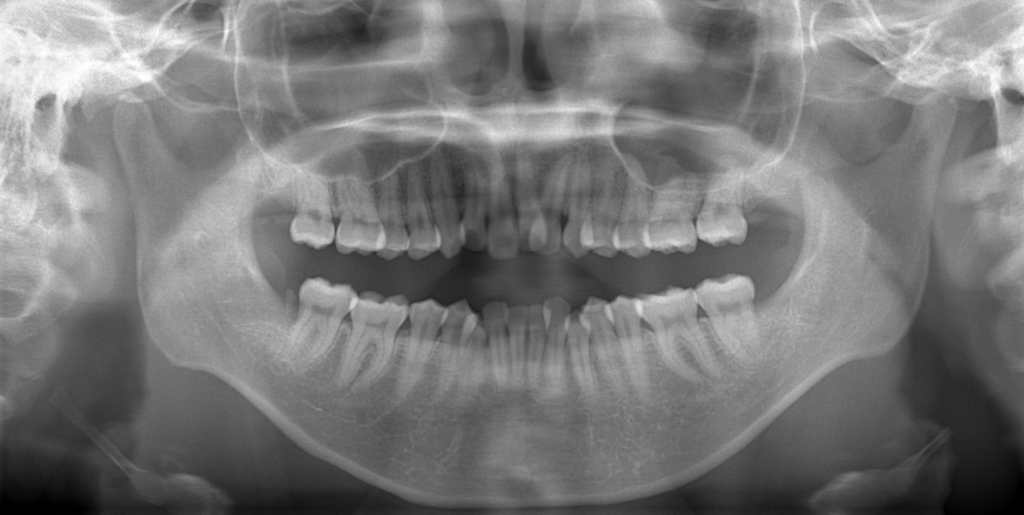

【Before】

レントゲン写真で確認すると、

この患者さんの場合、

【診断】

#1.(歯列の前方位による)上顎前突

#2.歯と顎の不調和による叢生(中等度)

と診断しました。